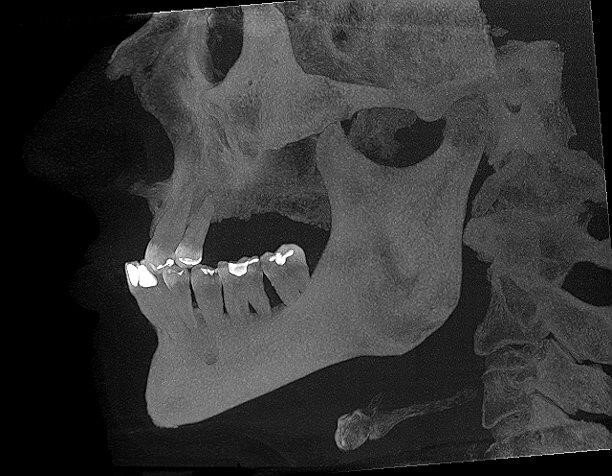

Wykonano CBCT, z którego wynikało, iż pacjent ma chorobę przyzębia. Zakwalifikowano wszystkie 10 zębów żuchwy do ekstrakcji. Zaplanowano zaopatrzenie pacjenta 8 implantami ICX oraz 5 implantami tymczasowymi Alpha Bio w celu wykonania pracy protetycznej tymczasowej bez obciążenia implantów docelowych ze względu na brak kontroli nad pacjentem w okresie wgajania implantów (zdjęcie CBCT oraz wewnątrzustne pacjenta). Za pomocą komputerowego systemu nawigacyjnego 3D został zaprojektowany szablon przytwierdzany 3 pinami do kości żuchwy w celu jego stabilizacji.